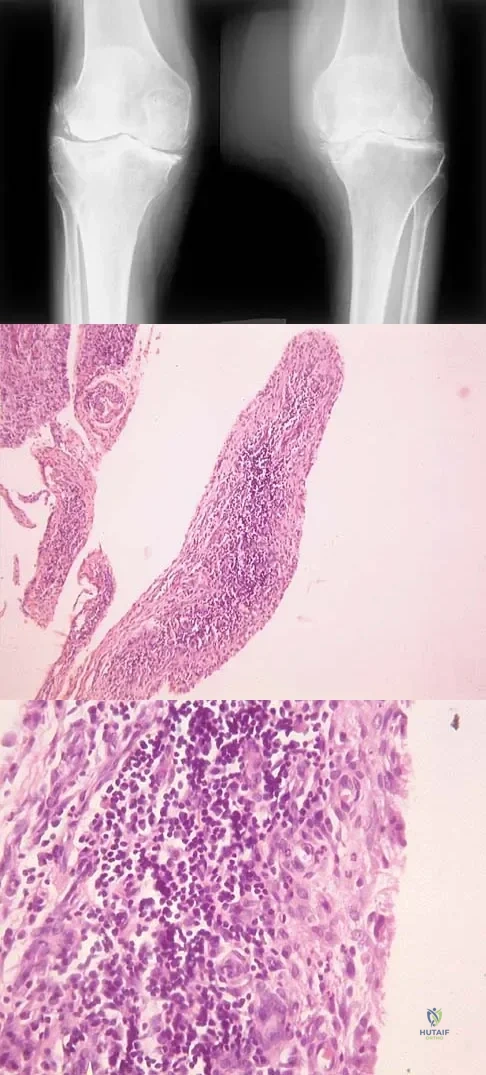

A 44-year-old woman has bilateral knee pain, and history reveals bilateral hip replacements. Radiographs are seen in Figure 28a, and histopathologic specimens from the total hip replacement are shown in Figures 28b and 28c. Laboratory studies reveal anemia. What is the most likely diagnosis?

Explanation